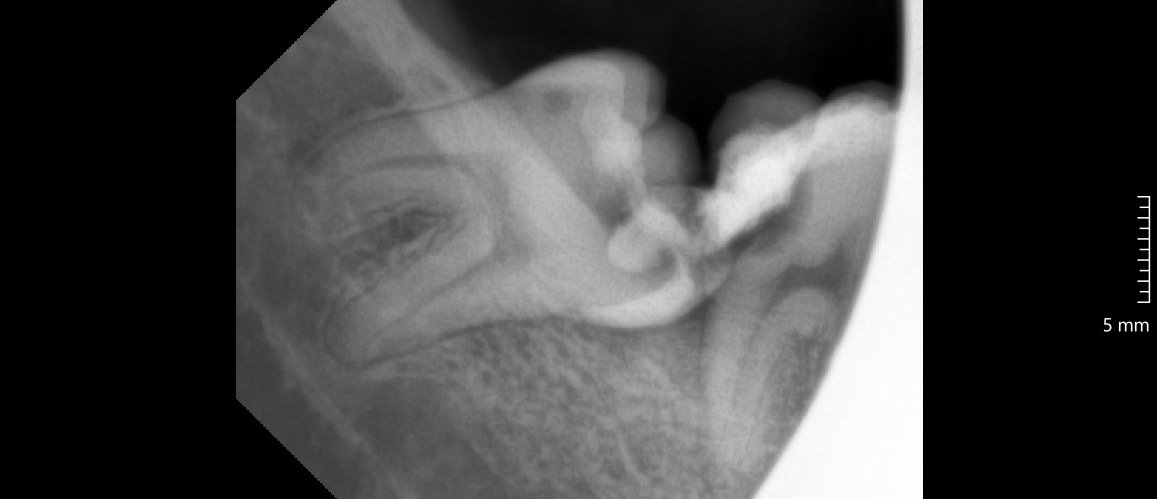

Odontektomi adalah prosedur bedah gigi untuk mengangkat gigi yang sulit dicabut dengan metode biasa. Dokter gigi biasanya melakukan tindakan ini pada gigi dengan impaksi, yaitu gigi yang tumbuh sebagian atau sepenuhnya terpendam di dalam gusi maupun tulang rahang.

Kasus paling sering yang membutuhkan odontektomi terjadi pada gigi bungsu (molar tiga). Gigi bungsu yang tumbuh miring atau kekurangan ruang di rahang sering menimbulkan nyeri, infeksi, serta gangguan pada gigi sebelahnya.

Dokter melakukan rontgen panoramic untuk melihat posisi gigi bungsu dan menilai kondisi pasien.